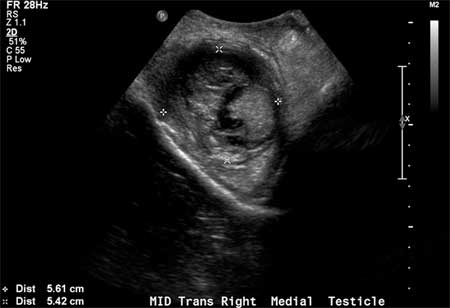

Ultrasound may show a break in the tunica albuginea, testicular contour irregularity, and poorly defined borders of the testicle.[Figure caption and citation for the preceding image starts]: Longitudinal grey-scale image of the medial right testicle shows a 5.4×5.6 cm intratesticular heterogenous focus with a peripheral hypoechoic rimBMJ Case Reports 2010; doi:10.1136/bcr.06.2010.3119 [Citation ends].com.bmj.content.model.Caption@6333ed81 Serum tumour markers are negative.